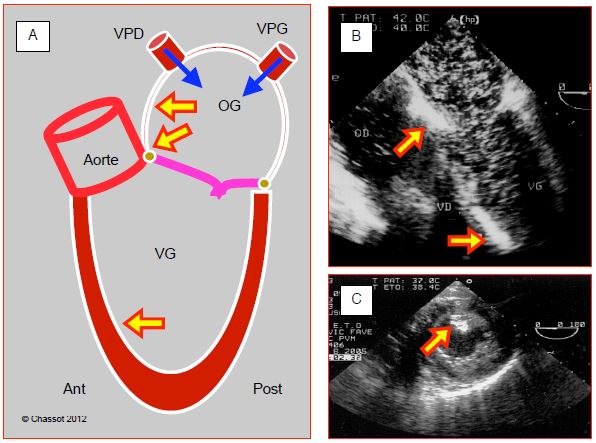

- 7.6.2 Purge des cavités gauches